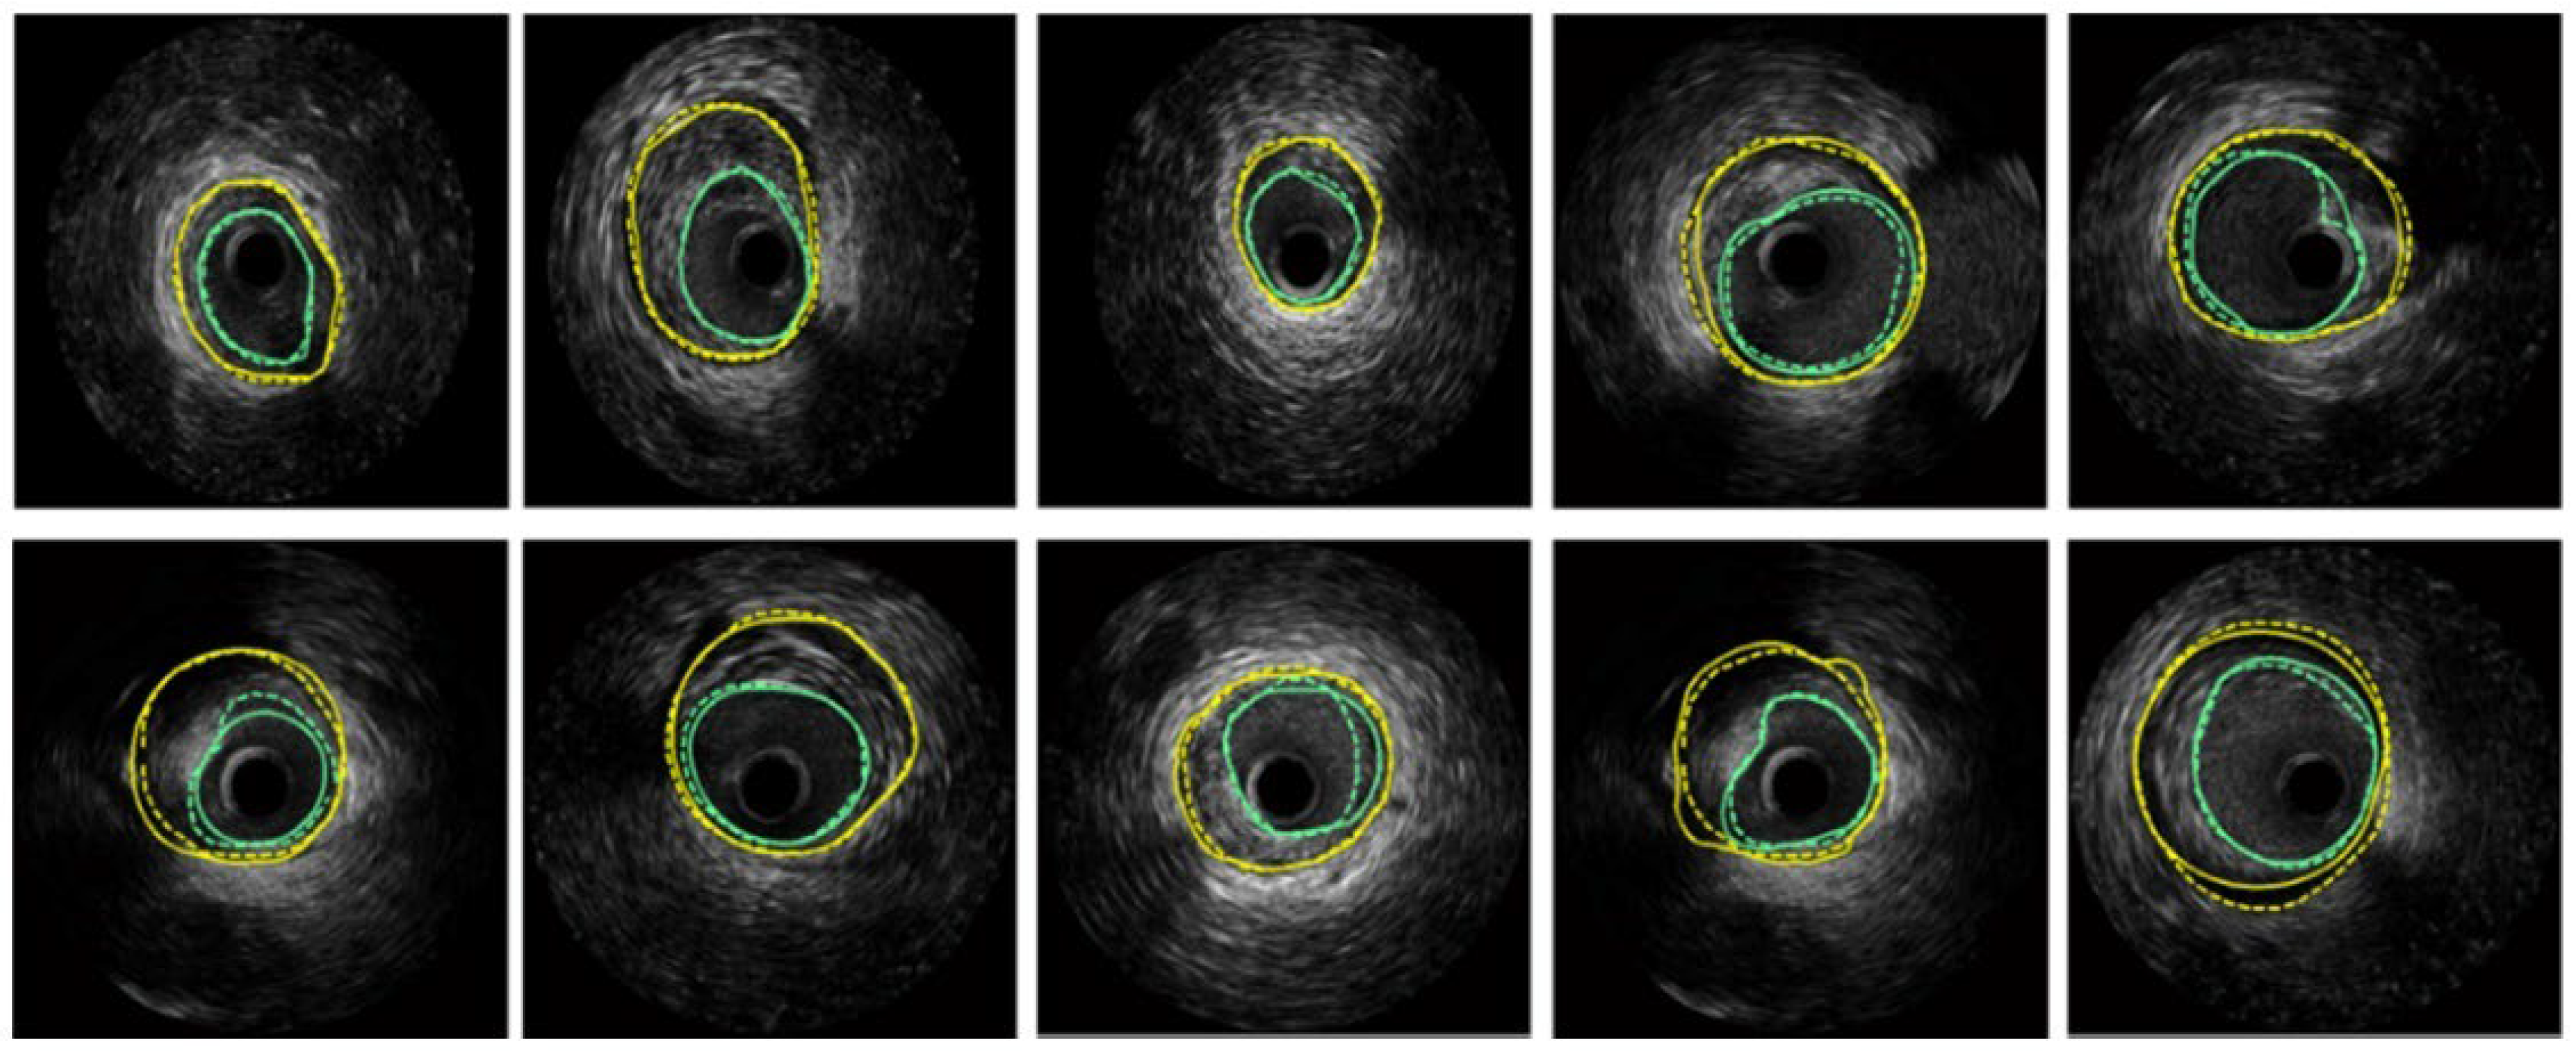

- Xia, M.; Yan, W.; Huang, Y.; Guo, Y.; Zhou, G.; Wang, Y. Extracting membrane borders in ivus images using a multi-scale feature aggregated u-net. In Proceedings of the 2020 42nd Annual International Conference of the IEEE Engineering in Medicine & Biology Society (EMBC), Montreal, QC, Canada, 20–24 July 2020; IEEE: New York, NY, USA, 2020. [Google Scholar]

| UNet and its variants (MFA-UNet) | Improves feature fusion and information retention, enables context retrieval from spatial-temporal perspectives | Complex architecture, may require large amounts of data for training | Optimized using Focal Tversky loss to address data imbalance | IVUS scan segmentation |